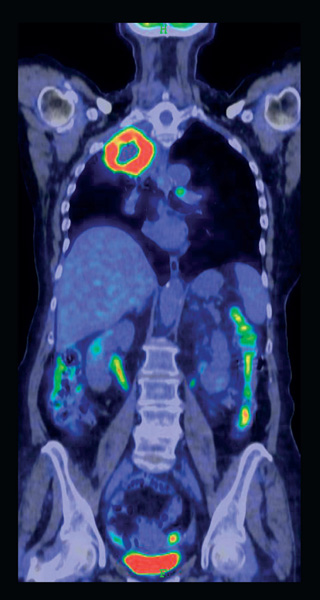

A NM létrejöttének alapja a radioaktív nyomjelzési technika kidolgozása volt, amelyért Hevesy György magyar származású vegyész 1943-ban kémiai Nobel-díjat kapott. Ennek lényege, hogy ha egy vegyület valamelyik atomját annak sugárzó izotópjával helyettesítjük, a kapott „radioaktívan jelzett” anyag kémiailag és biológiailag az eredeti, nem sugárzó vegyülettel azonosan viselkedik. Sugárzása segítségével nyomon követhetjük az adott vegyület (illetve származékai) mozgását, viselkedését kémiai reakciók és biológiai folyamatok során, akár egy élő szervezetben is külső sugárzásérzékelők segítségével. A mai műszerekkel olyan kis mennyiségű anyagot lehet sugárzása alapján kimutatni a szervezetben, amelynek jelenléte a vizsgálni kívánt szerv működését nem változtatja meg (ellentétben egyes röntgen-kontrasztanyagokkal), így lehetővé vált a funkció közvetlen leképezése.